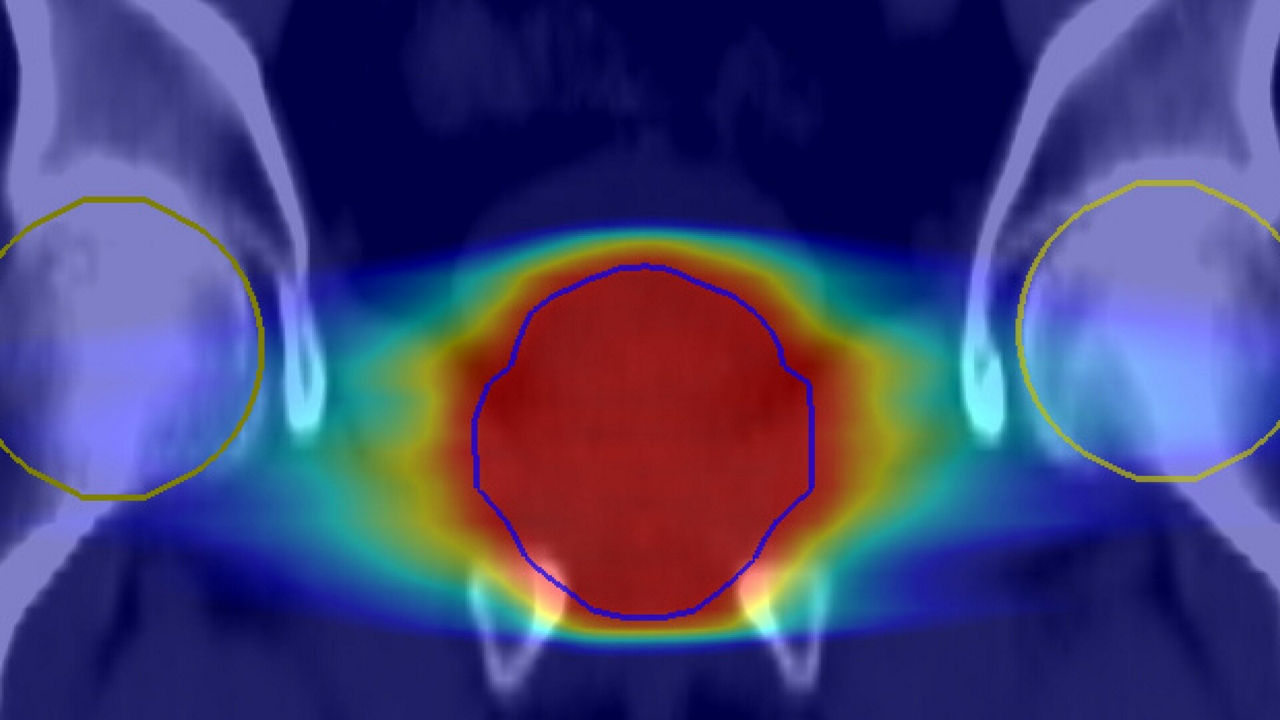

AIR™ RT Suite is compatible with iRT MR Direct and MRI planner, Spectronic Medical’s deep-learning-based pseudo-CT solution, which provides visualization of fiducial markers for position verification. It is also compatible with MR Contour DL, a deep learning-enabled auto organs-at-risk (OARs) segmentation solution for radiation therapy planning.